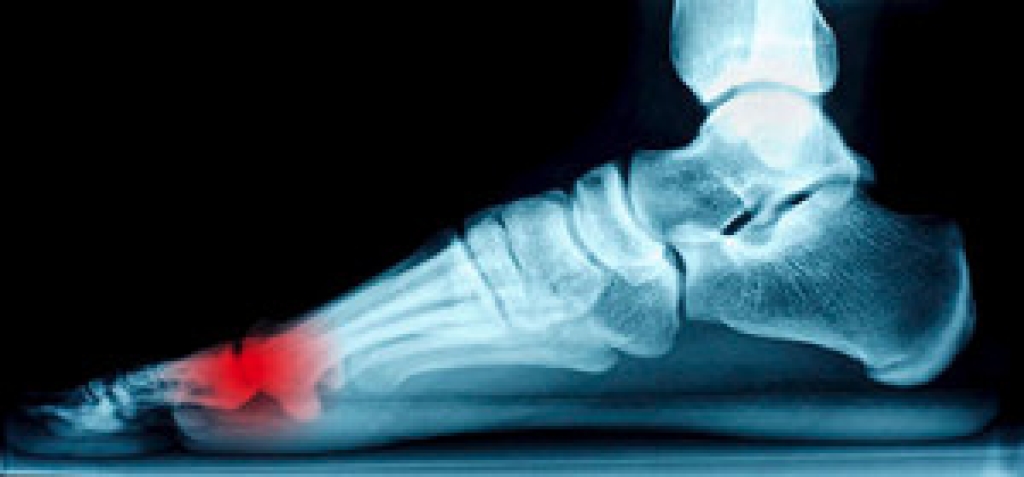

Standing on your feet for long periods of time can cause stress and pain in your feet. Your whole body may experience change in terms of posture, back pain, bunions, callouses and or plantar warts. There are ways to avoid these conditions with proper foot care, smart choices and correct posture.

Achilles tendon – Stretching the foot out flat on the floor will relax the calf muscles and tendon. These exercises can be performed almost anywhere. Make sure you add these exercises to your daily regimen.